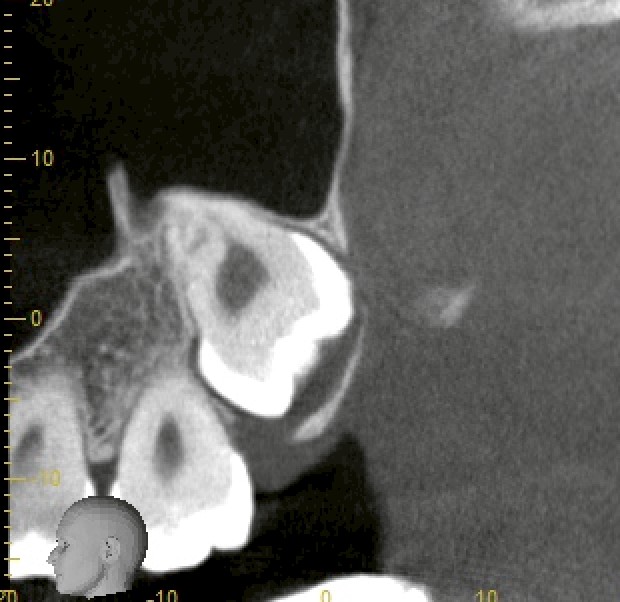

CTにて確認したところ、

・下顎:深い完全埋伏

・歯根は明らかに湾曲

・下歯槽神経に近接〜一部接触所見

・上顎:完全埋伏

・上顎洞に極めて近接

という状況でした。

いずれも「難易度が低い」とは言えないケースです。